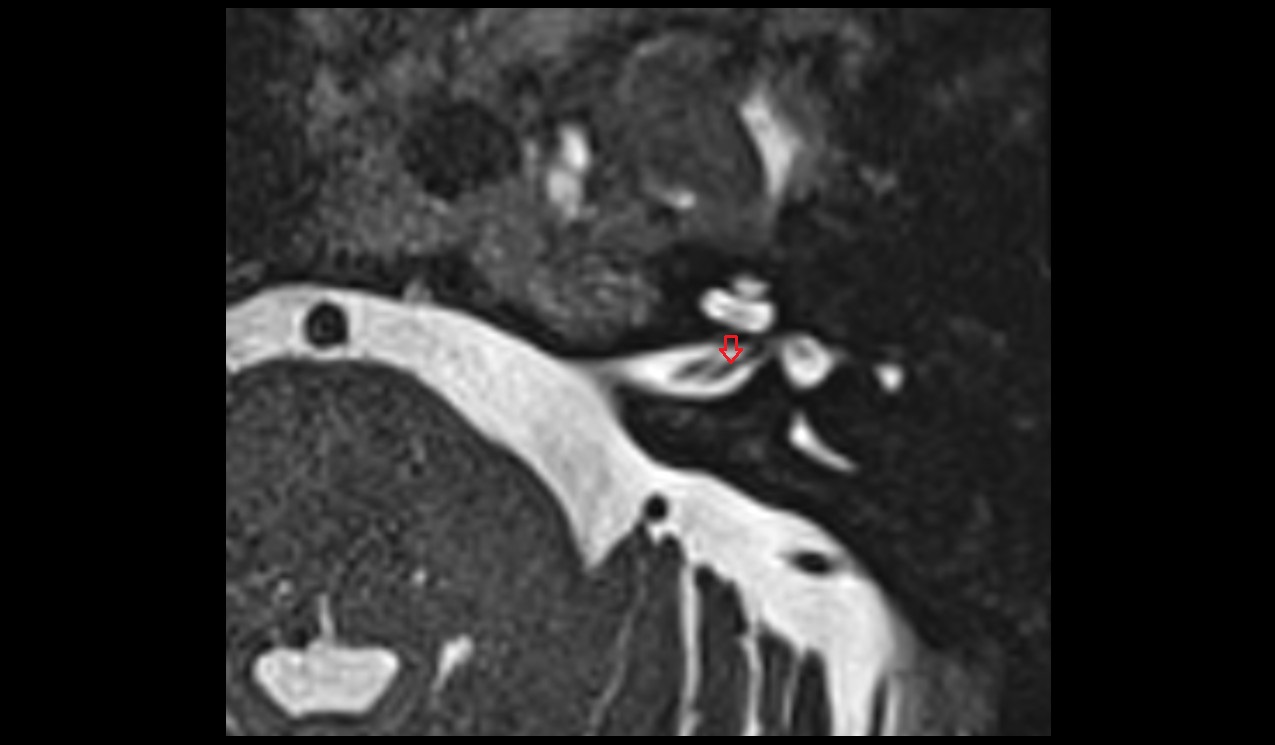

- Temporomandibular joint

- Articular disc of temporomandibular joint

- Articular eminence

- Mandibular condyle

- Mandibular fossa

- Superior head of lateral pterygoid muscle

- Inferior head of lateral pterygoid muscle